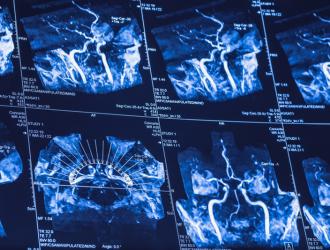

Uno studio internazionale su campioni di DNA appartenenti a oltre mezzo milione di individui provenienti da tutto il mondo ha identificato ventidue nuovi fattori di rischio genetici per l'ictus. Pubblicato su Nature Genetics, è il più grande studio genetico in materia.

L'ictus è nemico delle donne: colpisce più spesso lei che lui, e la mortalità è più alta per le donne rispetto agli uomini. Inoltre, le donne hanno fattori di rischio unici da cui i maschi sono esenti.

Nuove speranze per chi viene colpito da un attacco cerebrale. Un'innovativa terapia anti-neuroinfiammazione garantisce a chi ha subìto un ictus di recuperare il 50% dell'attività motoria in soli due mesi, più del doppio rispetto al miglioramento assicurato dal trattamento normale. E anche a seguito di...